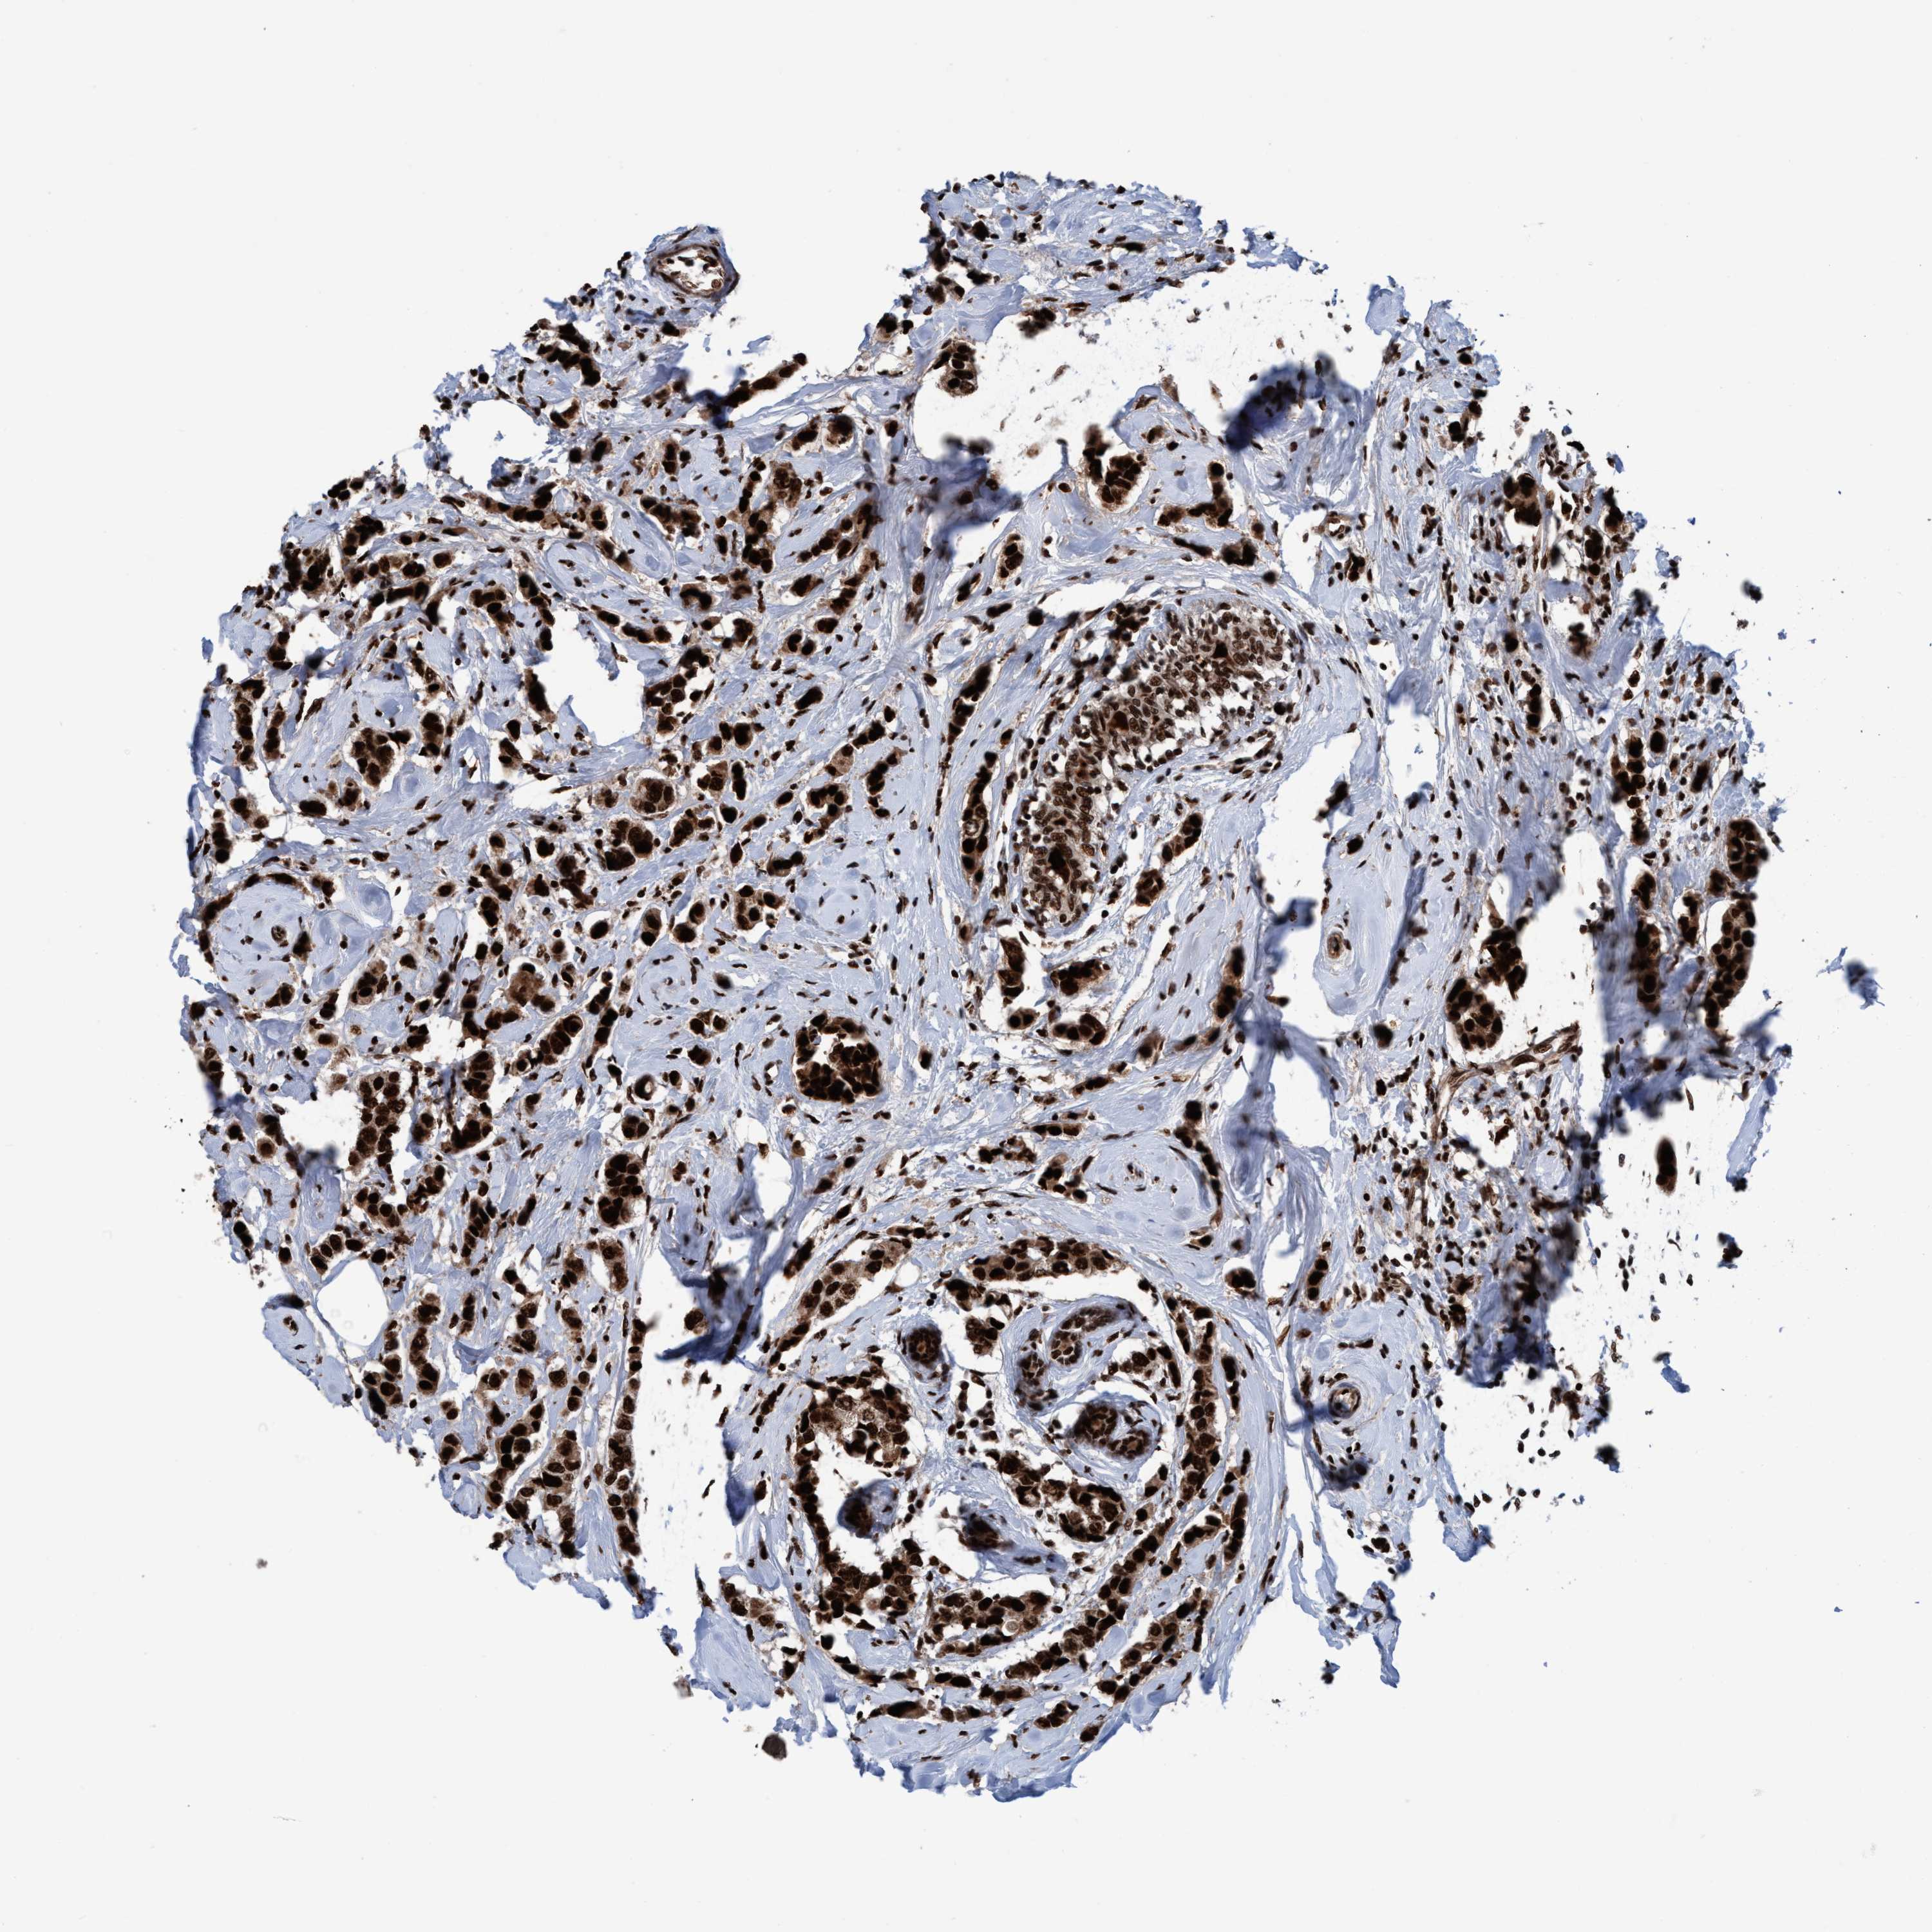

BRCA TCGA BRCA VALIDATION PROTEIN EXPRESSION